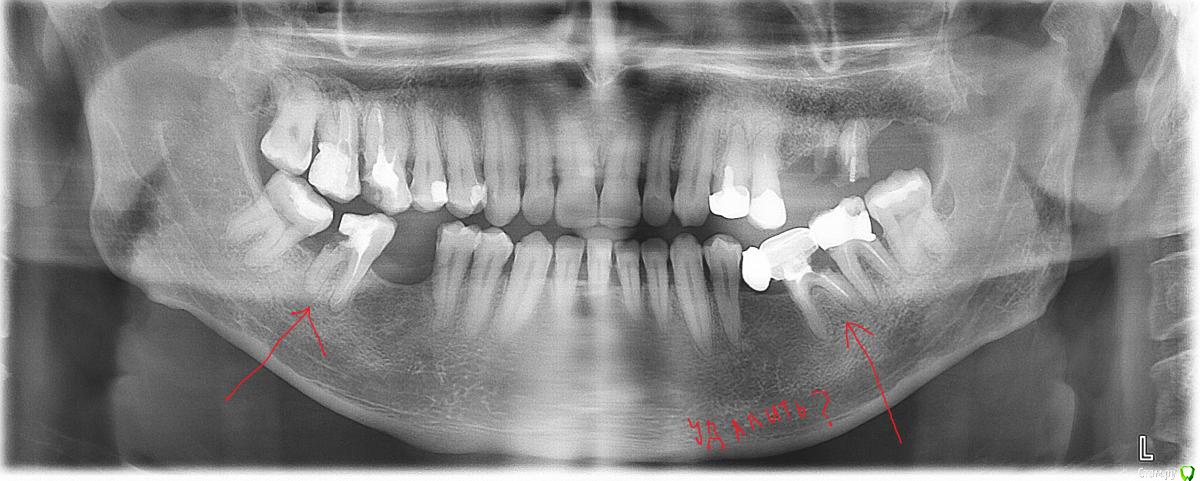

-SAE-Dantist_32 Опубликовано 15 апреля, 2015 Поделиться Опубликовано 15 апреля, 2015 Здравия желаю парни как вы думаете? всетаки на снос? Ссылка на комментарий

vitaliiPV Опубликовано 15 апреля, 2015 Поделиться Опубликовано 15 апреля, 2015 Удалять. Вы подумайте что останется после некротомии, будет ли там фуррул, или эти ткани которые останутся смогут противодействовать нагрузки. Оставите эти зубы - обязательно потеряете кость, в первую очередь в области фуркации. Вы не волшебник а врач, удаляйте и не переживайте Ссылка на комментарий

Чертков Александр Опубликовано 15 апреля, 2015 Поделиться Опубликовано 15 апреля, 2015 Без шансов...+1...и не только их 1 Ссылка на комментарий

Паращук Роман Опубликовано 16 апреля, 2015 Поделиться Опубликовано 16 апреля, 2015 Имхо удалять,но предыдущих коллег такое не смутило и 1.7 и 3.7 залепленно! )) Ссылка на комментарий

MenshikovDV Опубликовано 17 апреля, 2015 Поделиться Опубликовано 17 апреля, 2015 Вот как то так 1 Ссылка на комментарий

red_butler Опубликовано 18 апреля, 2015 Поделиться Опубликовано 18 апреля, 2015 Вот как то такЯ бы 2.4 2.5 пощадил Ссылка на комментарий

Alex52 Опубликовано 18 апреля, 2015 Поделиться Опубликовано 18 апреля, 2015 Я бы 2.4 2.5 пощадил Нафик нафикКорни короткие, нужен ретрит, феррула скорее всего нет 1 Ссылка на комментарий

voff Опубликовано 20 апреля, 2015 Поделиться Опубликовано 20 апреля, 2015 по верху- 24 я бы удалил, а остальные (ну кроме корней) покрутил на КТ Ссылка на комментарий

Bobby Опубликовано 20 апреля, 2015 Поделиться Опубликовано 20 апреля, 2015 Ортопантомограмма может давать приличное искажение. В данном кейсе нужно КТ покрутить - это профилактика подвигов по спасению безнадёжных зубов и наоборот овертритментов, когда удаляется то, что ещё может пожить. В целом, то что повычёркивали на предидущей страничке на орто верно, но лучше посмотреть тщательнее. Ссылка на комментарий

M@estro Опубликовано 20 апреля, 2015 Поделиться Опубликовано 20 апреля, 2015 Ну тогда уж и 2.2 удалять, кости -то нет вокруг. Пародонтоз.. Имхо 2.4, 2.5, если нет трещин - даже не подумал бы удалять. Тщательно посмотрел бы ещё 3.7 3 Ссылка на комментарий